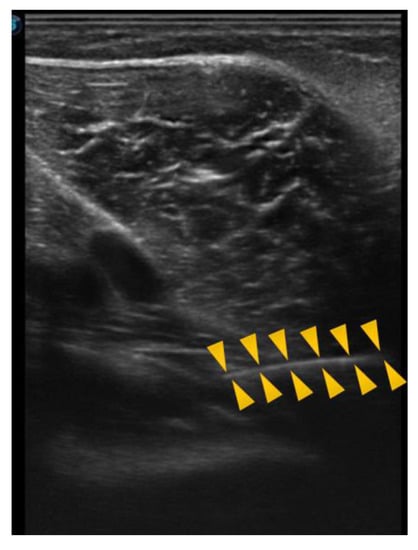

In the following image, obtained directly from the ultrasound scanner, we can see an example of a puncture, in which the needle, entering from the right side of the screen, directly reaches the popliteus in the internal superior region, which was the most frequently punctured region (Figure 6).

Figure 6.

Ultrasound of the popliteal puncture in the internal superior region. Head arrows define the needle line.